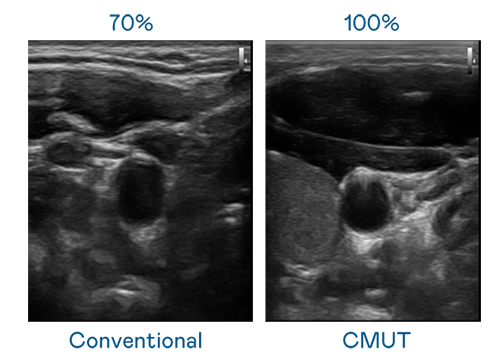

CMUT 技術是一種用電容式微機電元件來產生超音波訊號的技術。與傳統 PZT 壓電式技術相比,CMUT 頻寬增加 30%,更寬頻的超音波訊號讓影像解析度大幅提升,是實現高影像品質醫療超音波掃描、促進精準醫療發展的關鍵技術。

超音波影像的解析度高低,首先取決於探頭能發出的訊號頻寬。U8国际 CMUT 可提供高清晰的超音波訊號,提供高頻寬、高靈敏度、影像紋理細節更高的超音波影像,協助醫護人員縮短影像判讀時間及利用精準的醫療影像進行診斷。